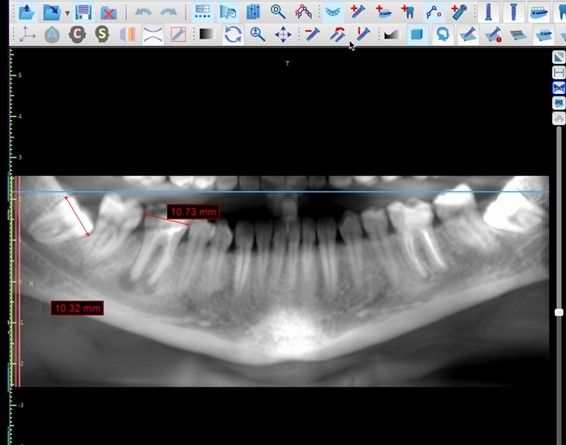

El autotrasplante dental es una opción terapéutica para aquellos casos en la que una pérdida dentaria es reemplazada por un diente donante del mismo paciente. Este autotransplante colocado en el alveolo puede ser inmediato o diferido. Suele estar indicado en paciente joven, siendo más frecuente el autotransplante de cordal a primer o segundo molar, y el de premolar a incisivo. El diente donante debe reunir unos criterios clínicos que aumenten el éxito de la técnica, basados en la morfología, el estadio de desarrollo radicular y la salud periodontal. La planificación se llevará a cabo con un CBCT y simulación virtual que genere un prototipo réplica en 3D; esto permite evaluar las dimensiones del diente donante para su correcta colocación en el alveolo receptor.

Se reporta el caso de un autotrasplante del tercer molar inferior derecho al alveolo postextracción de un primer molar inferior, en una paciente de 22 años de edad. Actualmente, el autotransplante se considera una opción de tratamiento si se siguen los criterios de selección del caso adecuados, y se realiza una técnica quirúrgica protocolizada. El diagnóstico planificado mediante CBCT, la simulación virtual y la confección de una réplica en 3D optimiza la técnica de forma segura, predecible con tiempos de cirugía menores.

El sitio receptor debe garantizar la adaptación del diente donante, se realizará un diagnóstico mediante planificación con CBCT que permita segmentar virtualmente el diente donante y llevarlo digitalmente al sitio receptor3.

La confección de la réplica 3D del diente se ha de realizar con material biocompatible y esterilizable mediante radiación gamma y beta. La ventaja del modelo estereolitográfico es minimizar el tiempo extraoral del diente donante, el daño al ligamento periodontal, así como poder remodelar el alveolo receptor sin usar el diente donante5,13,14.